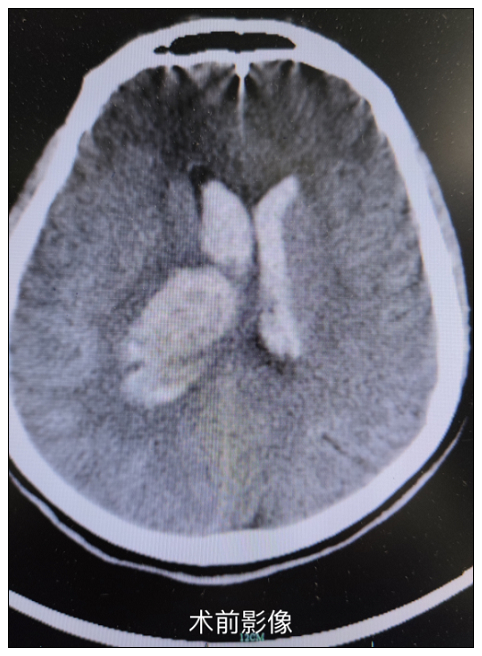

患者因“突发意识不清三小时”入院,急诊来院时深昏迷,刺激四肢无明显活动。CT检查示:右侧背侧丘脑出血量约12ml,两侧额叶腔隙性脑梗塞,脑室积血铸型。患者既往有高血压病史,病情危重,需急诊手术治疗。

神经外科团队接诊后,急诊为患者在气管插管全麻下行内镜辅助下脑室血肿清除+丘脑血肿清除+左、右脑室外引流+颅内压探头植入术。术中仔细清除脑室血肿约20ml及丘脑血肿,经充分有效的止血,术中失血量约30ml。手术三小时不到,术后返回神经外科监护室行进一步抢救治疗。经过精心治疗和护理,患者一天天恢复。术后患者恢复良好,神志清楚,头部切口愈合可,右侧肢体可见活动,左侧偏瘫,顺利出院。